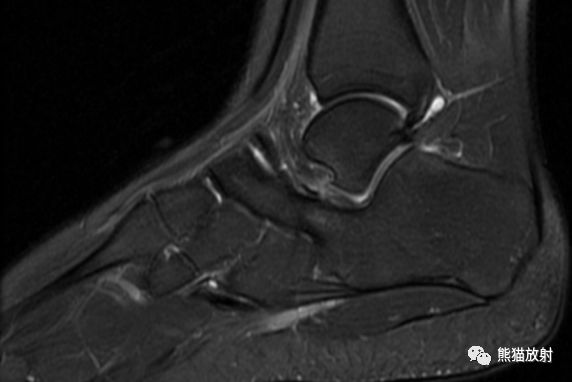

MR矢状PD压脂、矢状T1WI;主要表现:跟骨和舟骨之间可见骨性联合,MR上相应区域无水肿